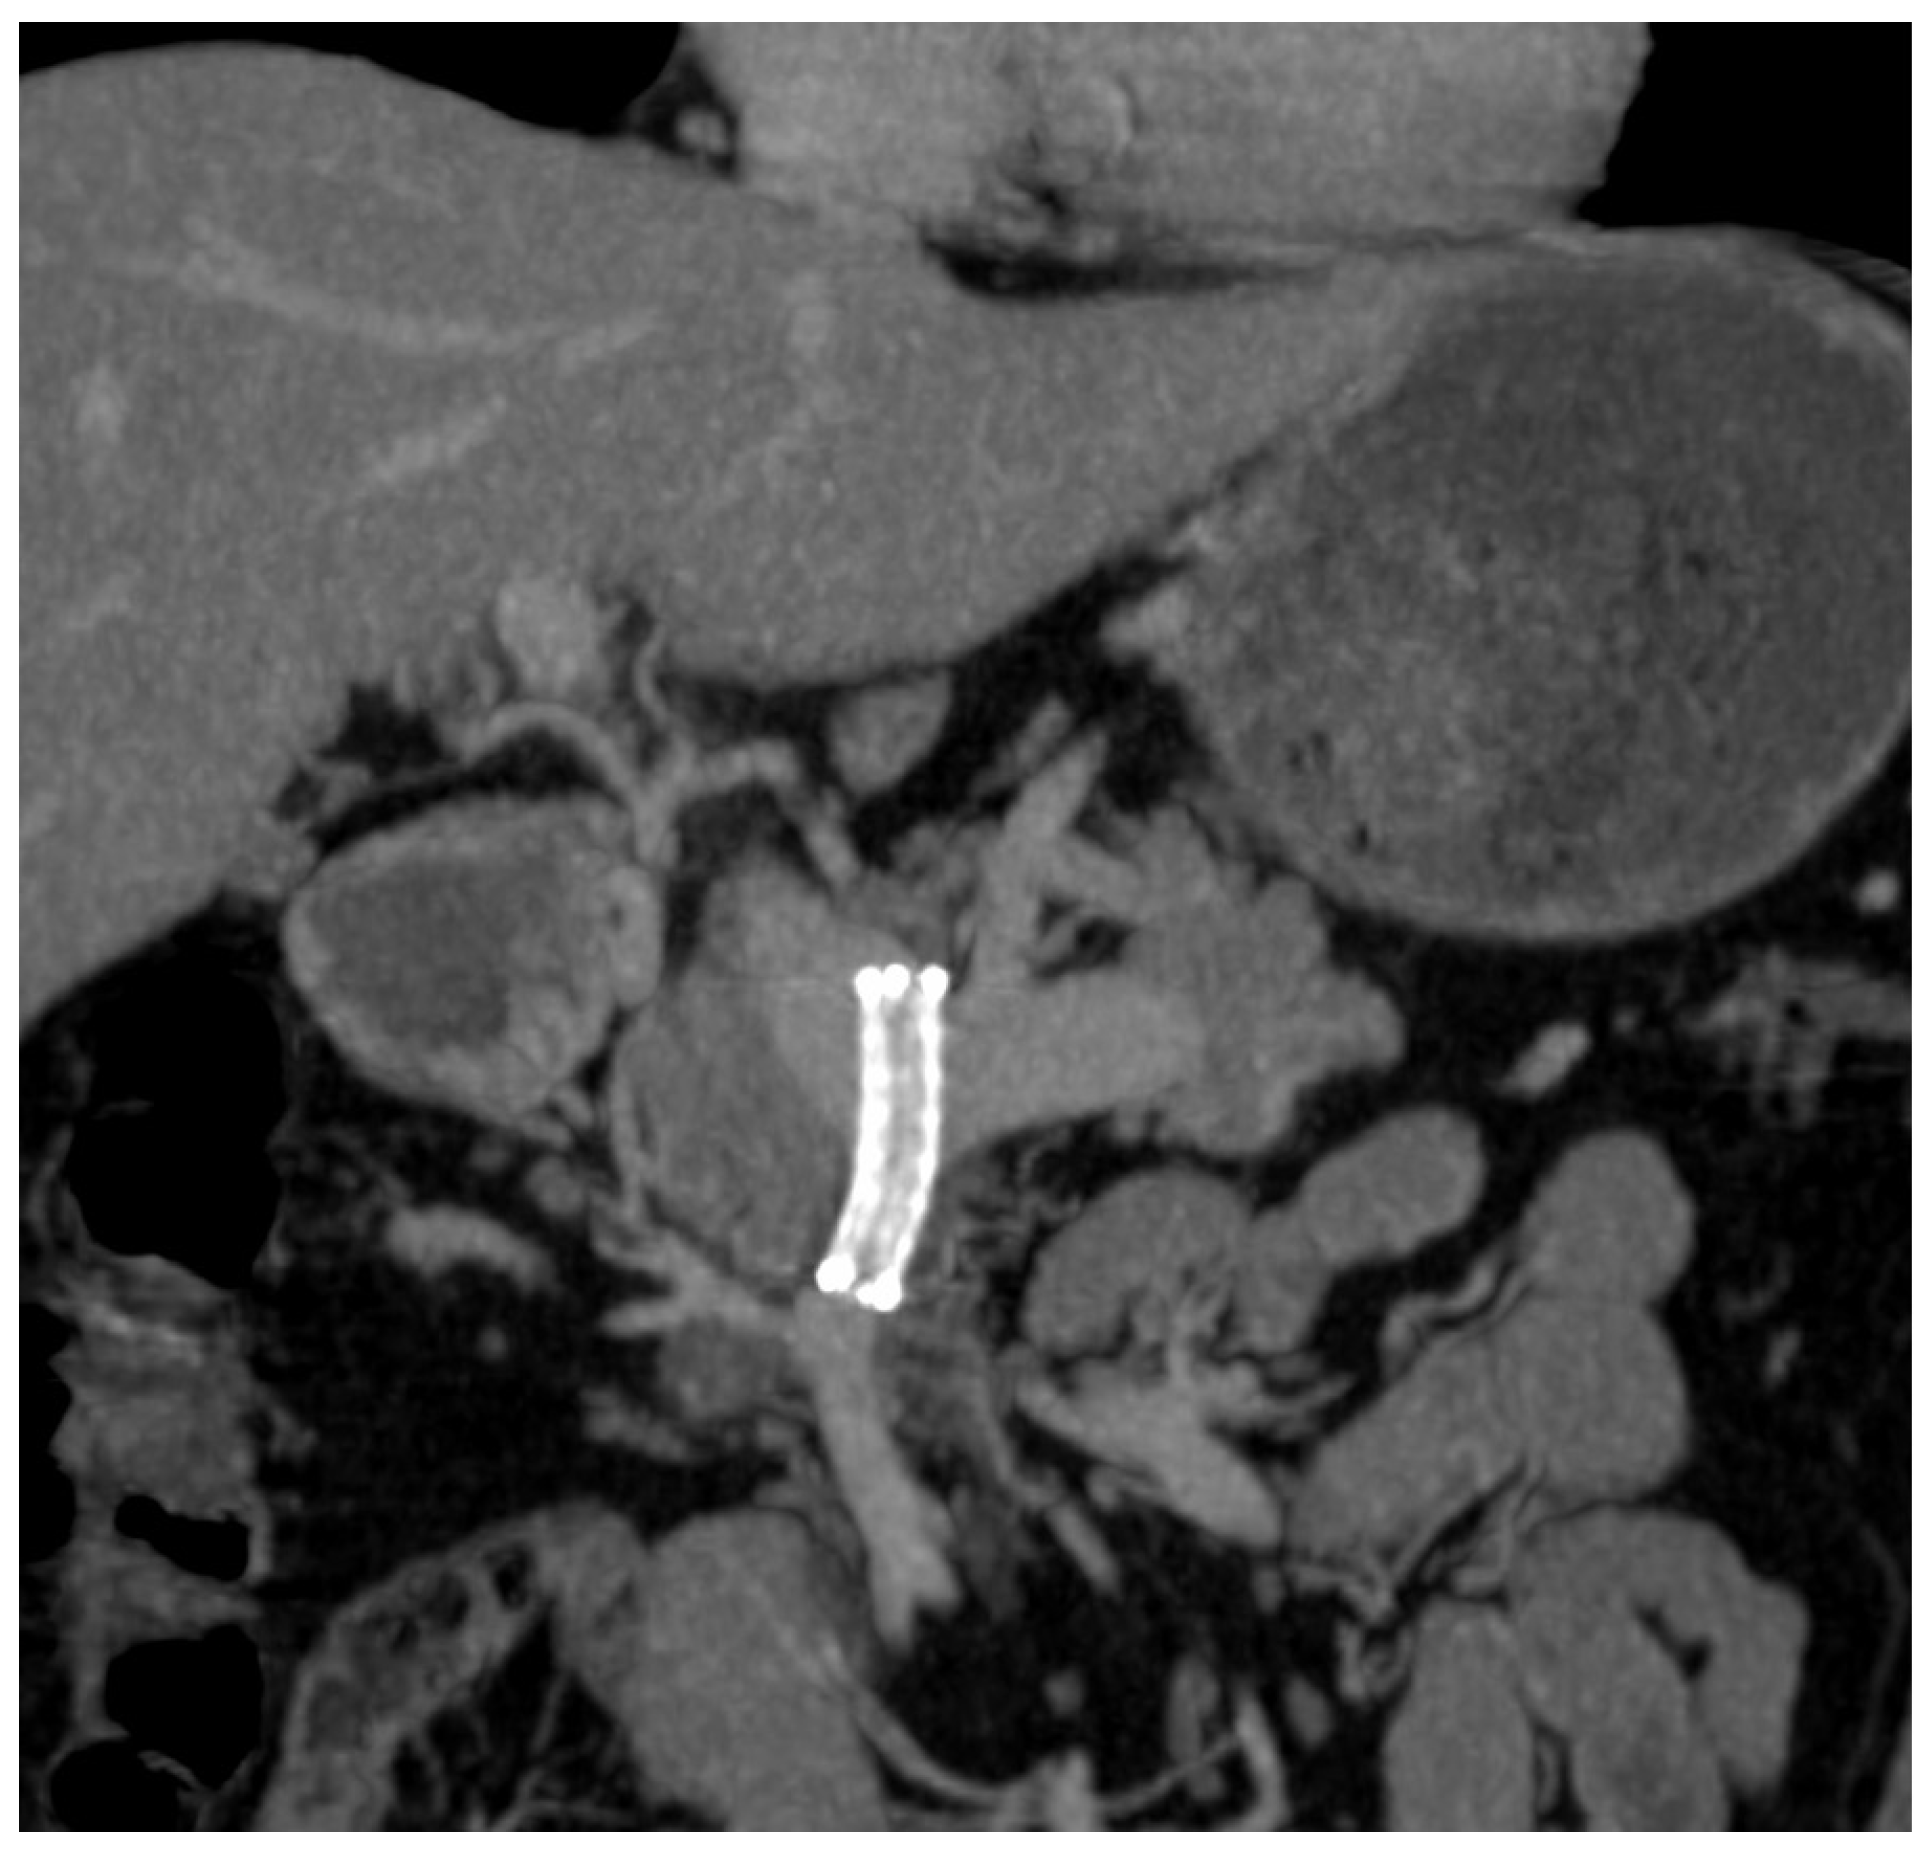

2. Case Report